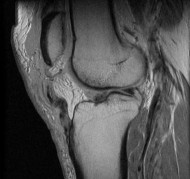

Question 13:

During posterior cruciate ligament (PCL) reconstruction, understanding bundle biomechanics is essential. Which of the following best describes the function and tensioning pattern of the native PCL bundles?

Correct Answer: The anterolateral bundle is the primary restraint to posterior translation at 90 degrees of flexion and tightens in flexion

The PCL consists of the larger anterolateral (AL) bundle and the smaller posteromedial (PM) bundle. The AL bundle is lax in extension and becomes tight in flexion, acting as the primary restraint to posterior tibial translation at 90 degrees of knee flexion. Conversely, the PM bundle is tight in extension and lax in flexion.